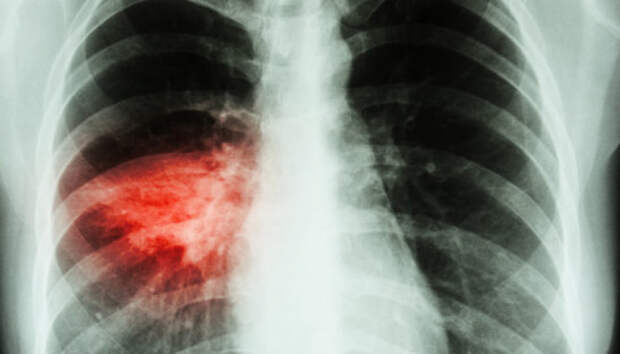

Всем пациентам с воспалением легких неоднократно проводится исследование на COVID-19 Двенадцать человек за сутки госпитализированы с внебольничной пневмонией в Карелии, сообщает оперштаб по борьбе с распространением коронавирусной инфекции. Летальных исходов не зарегистрировано. Начиная с 1 апреля с внебольничной пневмонией госпитализированы 1160 пациентов, 72 человека умерли (с учетом пациентов, госпитализированных ранее указанного периода).